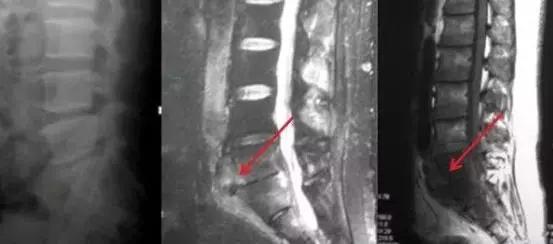

1、 这个患者是年轻男性,他因腰痛就诊。影像检查发现腰骶椎结核,从核磁看(红色箭头示)腰骶椎体有炎性表现,椎间隙狭窄,椎前有脓肿。

患者的腰痛不严重,可以下地活动,脓肿也不大。给予保守治疗,患者每个月门诊复查一次,通过影像及化验检查定期观察治疗效果及药物副作用,根据结果动态调整治疗药物,用药一年后,患者疼痛缓解,从核磁看(红色箭病灶吸收,达到治愈。